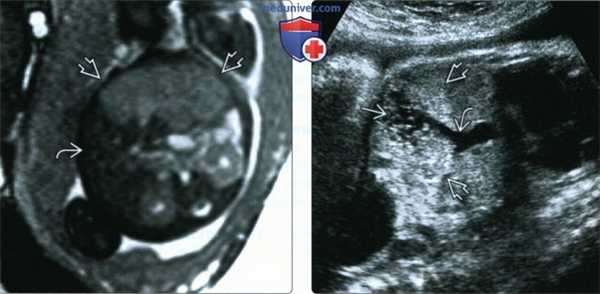

(Слева) МРТ плода в 34 нед., Т2-ВИ, поперечная плоскость. В толще нормальной гипоинтенсивной печени плода визуализируется четко очерченное умеренно гиперинтенсивное образование.

(Справа) УЗИ того же плода, сагиттальная плоскость, косой срез. Визуализируется гиперэхогенное образование с кистозными включениями. Предположить сосудистую природу образования можно по крупной отводящей вене (допплерография подтвердила наличие кровотока). В 38 нед. появились признаки водянки плода, было выполнено экстренное родоразрешение.